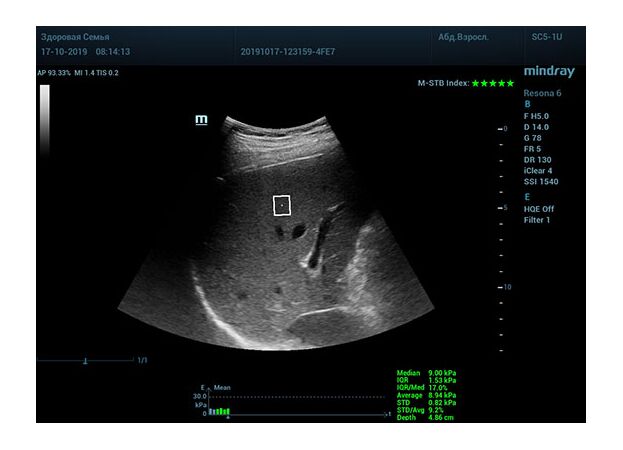

Определение плотности печени. Не ошибся ли оператор при измерении эластических свойств печени? Для оценки критериев качества предусмотрен индекс MBT, который покажет насколько «твердой» была рука оператора и двигалась ли печень. При MBT 5* рука тверда и показатели достоверны. Для оценки качества результатов используется IQR индекс, отображающий колебания показателей в точке измерения при расчете медианы. Показатели при IQR <30% считаются приемлемыми. Техника сканирования через межреберные промежутки требует размещение окна интереса на несколько сантиметром ниже капсулы, для исключения эффекта реверберации. Установка ROI на паренхиму без захвата сосудов, для исключения погрешностей измерения.

Стадия фиброза определяется по системе METAVIR Staging, построенной на данных биопсии и сопоставлении с данными эластографии. Своевременная диагностика фиброза, и начало его лечения, залог благоприятного исхода заболевания.

• METAVIRF0 – норма.

• METAVIRF1 – Портальный фиброз без вовлечения перегородок

• METAVIRF2 – Портальный фиброз с вовлечением нескольких перегородок

• METAVIRF3 – Портальный фиброз с вовлечением множества перегородок

• METAVIRF4 – Цирроз.